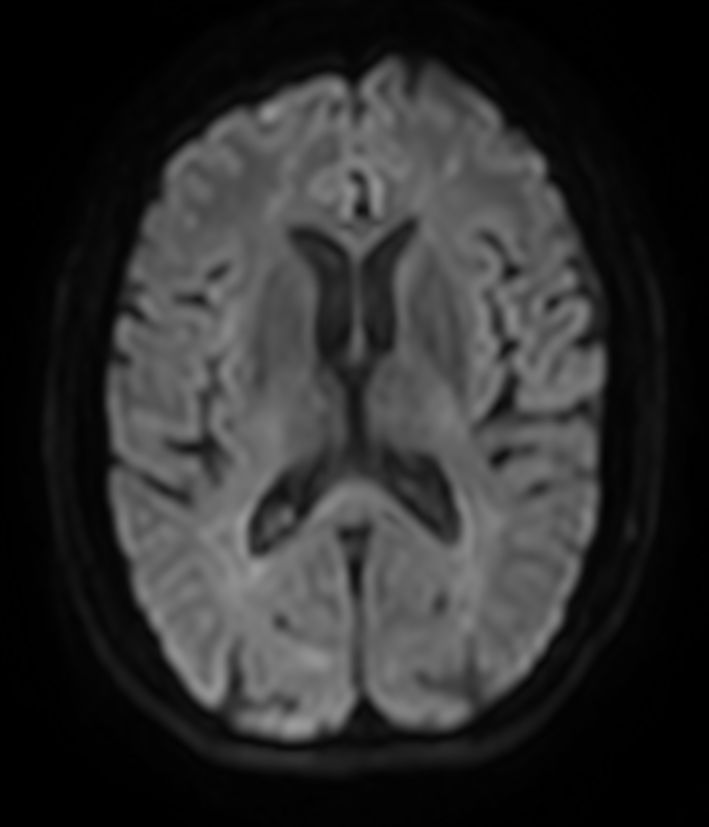

DWI b1000

DWI b1000 (ADC)